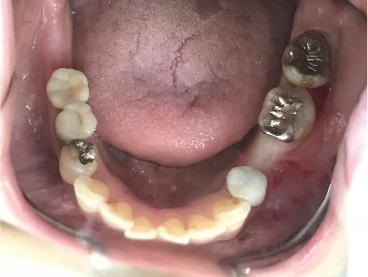

下、左右歯がないところに歯を入れたい。

右下に2本、左下に1本インプラントを入れました。

所感

下顎左右奥の歯がないところに、インプラント治療を希望されて来院されました。X-Guideを使用し埋入しました。治療後「左右の奥歯でしっかり噛めてうれしいです。」と、とても喜んでくださいました。

Before